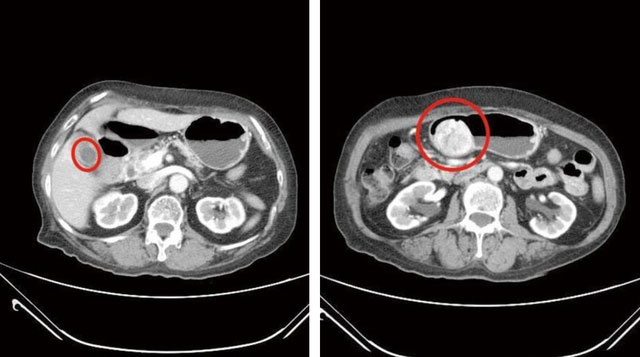

Khám tiêu chảy, người phụ nữ ngỡ ngàng phát hiện túi mật đầy sỏi, khối u 6cm trong bụng-1Hình ảnh CT nhân vật bị sỏi và viêm túi mật (trái), đồng thời có khối u mô đệm đường tiêu hóa 6cm trong dạ dày (phải)

Sau khi nội soi tiêu hóa trên và chụp CT, các bác sĩ phát hiện cùng lúc bà gặp phải 2 vấn đề nghiêm trọng trong ổ bụng. Một là sỏi chất đầy trong túi mật và hai là khối u dạ dày loại mô đệm đường tiêu hóa 6cm. Điều đáng nói là khối u này không phải mới xuất hiện mà đã được nghi ngờ từ 3 năm trước nhưng bà Lin không chịu thăm khám chuyên sâu, cũng cho rằng không có triệu chứng khó chịu rõ ràng.